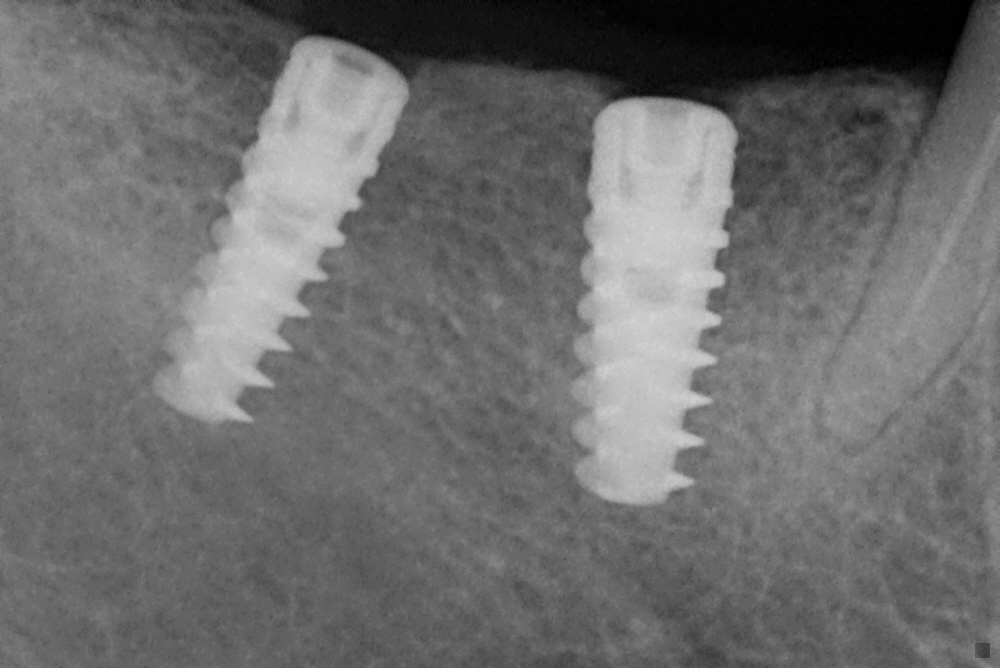

Enter dental implants, a revolutionary service at Malhar Dental Clinic. Dental implants are not just about filling gaps; they are about restoring the foundation of a person’s smile and, consequently, their confidence. Dr. Priya explained to Ramesh how these implants, once placed, would integrate with his jawbone, providing the strength and functionality of natural teeth. This wasn't just a dental procedure; it was a life-changing experience.

Ramesh’s journey with Malhar Dental Clinic began with a comprehensive consultation. Dr. Priya and her team took the time to understand his needs, fears, and expectations. Using state-of-the-art technology, they crafted a personalized treatment plan that promised a seamless and pain-free experience. The clinic's commitment to using only the highest quality materials ensured that Ramesh's new tooth would not only look natural but would last a lifetime.